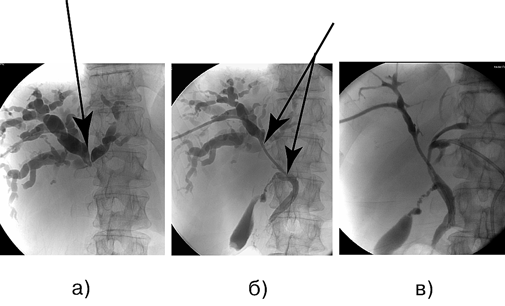

Рисунок 4. Больной К., 61 год. Аденокарцинома проксимального отдела внепечёночных желчных протоков (опухоль Клатскина), Bismuth — IV тип, состояние после раздельного чрескожного чреспеченочного дренирования протоков правой и левой доли печени:

а — ЧЧХС, наружное дренирование, холангиография, блок на уровне конфлюэнса желчных протоков; б — ЧЧХС, наружно-внутреннее дренирование, холангиография, блок на уровне конфлюэнса желчных протоков; в — ЧЧХС, раздельное наружно-внутреннее дренирование долевых протоков, холангиография, блок на уровне конфлюэнса желчных протоков